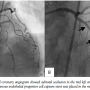

A 78-year-old man was referred for intermittent chest pain during preoperative risk assessment for stomach cancer. Echocardiogram showed anterior wall motion abnormality during chest pain. Coronary angiogram revealed tight stenosis in the mid left anterior descending (LAD) coronary artery (Figure 1A). In anticipation of the urgent surgery and chest pain due to unstable angina, plain old balloon angioplasty (POBA) was applied to the stenotic lesion. However, there was still significant residual stenosis and minor dissection was

suspected after POBA. It seemed that the deployment of a stent was inevitable. An endothelial progenitor cell (EPC) capture stent (Genous; Orbus Neich Medical Technology) was implanted (Figure 1B) to promote reendothelialization by CD 34 antibodies attached to stent struts. The patient was started on dual antiplatelet therapy after the procedure. Two weeks later, the patient underwent repeat coronary angiography and optical coherence tomography (OCT). There was no in-stent restenosis; however, two newly developed small aneurysms were found behind the stent struts (Figure 2). All stent struts were covered on OCT.